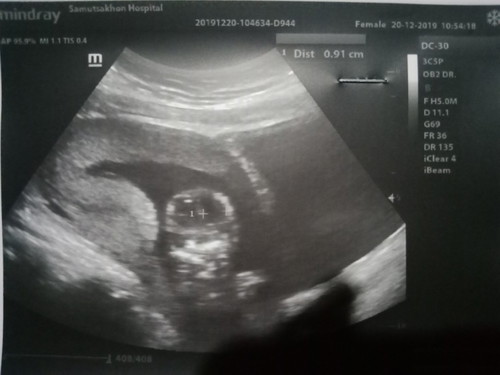

ดูเพศตรงไหนค่ะ

หญิงค่ะแม่ Female ข้างบนค่ะ วันที่ 20

ดูไม่เป็นอ่ะ😁😁